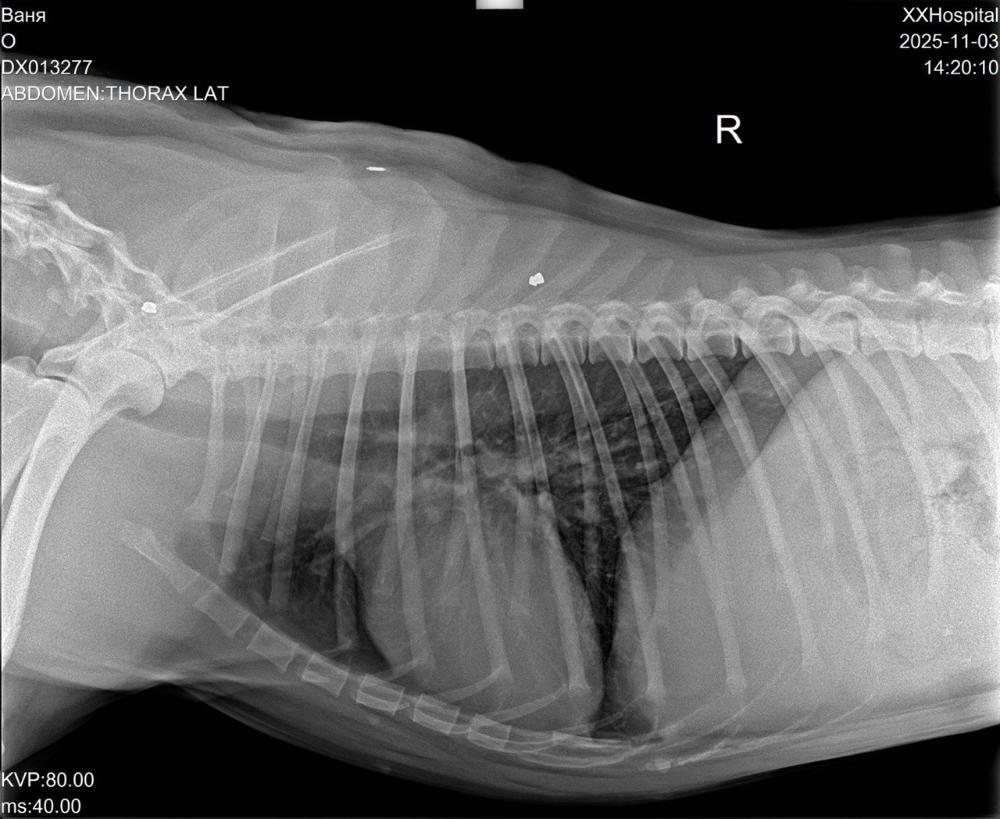

Вячеславовна Опубликовано 4 ноября Опубликовано 4 ноября Новости от Ванюши🙏💕 Вчера вечером начали переливание крови, перелили 200 мл крови и началась аллергическая реакция. Скорее всего реакция на инородный белок. Кровь проверяли на совместимость несколько раз. Ночью Ванюшу капали, снимали аллергическую реакцию. Находится под наблюдением. Сегодня с утра продолжили капать. Отёк сняли, температура в норме, давление держит, писает, какает, кушает сам, хвостиком виляет. Ближе к вечеру будут мониторить состояние Вано. Ждём обратную связь. Ванюша очень нужна наша помощь!!! Пока в теме небольшой минус, но сегодня вечером будет выставлен счёт😱 Реквизиты для помощи Карта СБ привязана к номеру 8 964 517 25 21 на Ирина П. с пометкой "Вано". 1 2

Вячеславовна Опубликовано 5 ноября Опубликовано 5 ноября Всем привет от Вано! 💕 Состояние у мальчонки стабильное, готовится сегодня к вечеру к выписке, Илья Ванюшку заберёт домой🙏😍 При выписке нужно будет оплатить почти двое суток стационара ( это больше 30000р.), в теме уже минус((( Помощь Вано очень актуальна🙏 🆘🚨🆘🚨🆘🚨🆘🚨🆘🚨🆘🚨🆘🚨🆘 Реквизиты для помощи Карта СБ привязана к номеру 8 964 517 25 21 на Ирина П. с пометкой "Вано". 1 1